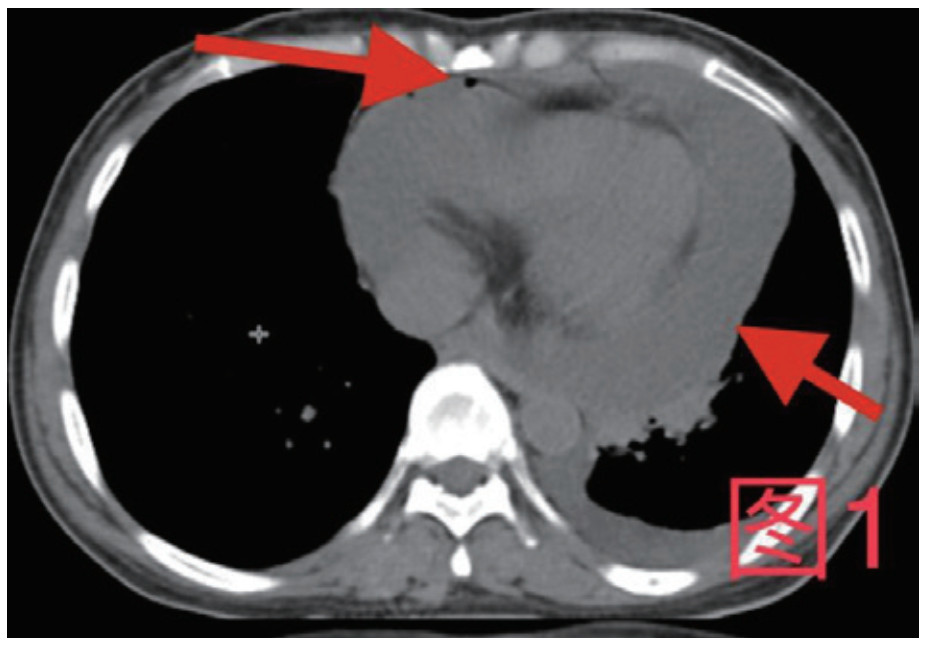

患者,女,41岁,2020年10月26日因“腹痛3 d”入急诊,否认近期有吞服异物、鱼刺、骨头等,无腹部手术史。入院查体:体温36.9℃,心率115次/min,血压98/57 mmHg(1 mmHg=0.133 kPa),血氧饱和度:97%;腹软,上腹部压痛,腹肌略紧张,余查体阴性。入院初检验:乳酸13.3 mmol/L;超敏C反应蛋白212.46 mg/L;血常规白细胞计数35.0×109/L,中性粒细胞百分数0.908,降钙素原50.46 ng/mL;Pro-B型钠尿肽7 117 pg/mL;肌钙蛋白T 0.147 ng/mL;肌酐554 μmol/L,谷丙转氨酶2 499 U/L,谷草转氨酶5 908 U/L。心电图未见ST-T改变;胸腹部增强CT(图 1、图 2):示大量心包积液伴少许积气,纵隔少量积气;左侧少量胸腔积液,右肺下叶感染,盆腔少量积液;心脏超声:心包积液(大量),最深处21 mm;急诊予心包穿刺引流出大量浑浊脓性液体,心包穿刺引流液常规:中性粒细胞占96%,涂片见革兰阴性杆菌及革兰阳性球菌,积液培养见咽峡炎链球菌。诊断:化脓性心包炎,脓毒血症,多脏器功能不全,代谢性酸中毒。本病例报道经温州医科大学附属东阳市人民医院伦理委员会批准,且所有临床检测指标及有创操作均获得家属同意或直系亲属的授权(伦理审批号:东人医2021-YX-124)。

| 图 1 箭头所指为心包内积气积液 |